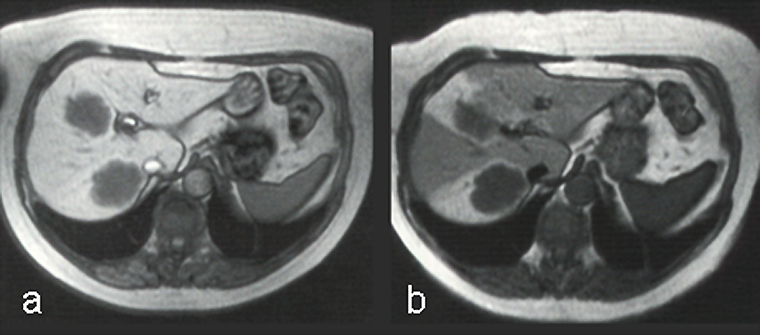

Mn-DPDP (Figure 13-16) is a positive multipurpose agent ta­ken up by, e.g., the he­pa­to­cytes [⇒ Rummeny 1997]. The contrast enhancement seems to be connected to a limited release of manganese ions. The enhancement is long last­ing and can be achieved with low doses. While on the market for liver applications, mangafodipir was the preferred agent in patients with kidney problems. Oral or intravenous MnCl2 can have a similar effect.

Figura 13-16:

The uptake of Mn-DPDP (mangafodipir) in the liver relies on the ability of hepatocytes to excrete metal ions. Manganese separates from the DPDP-complex and is taken up by the hepatocytes.

T1-weighted GRE images. (a) The metastases are well delineated 15 minutes after the injection, and (b) even 24 hours after administration some of the contrast agent remains.